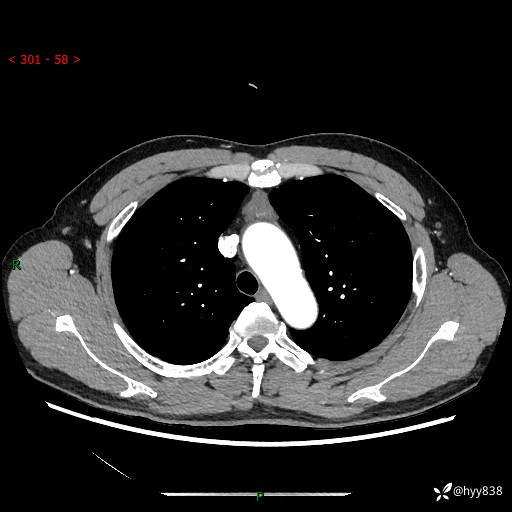

患者性别:女

患者年龄:49岁

简要病史:跟骨骨折,常规CT发现纵隔占位

增强(动脉期+静脉期)